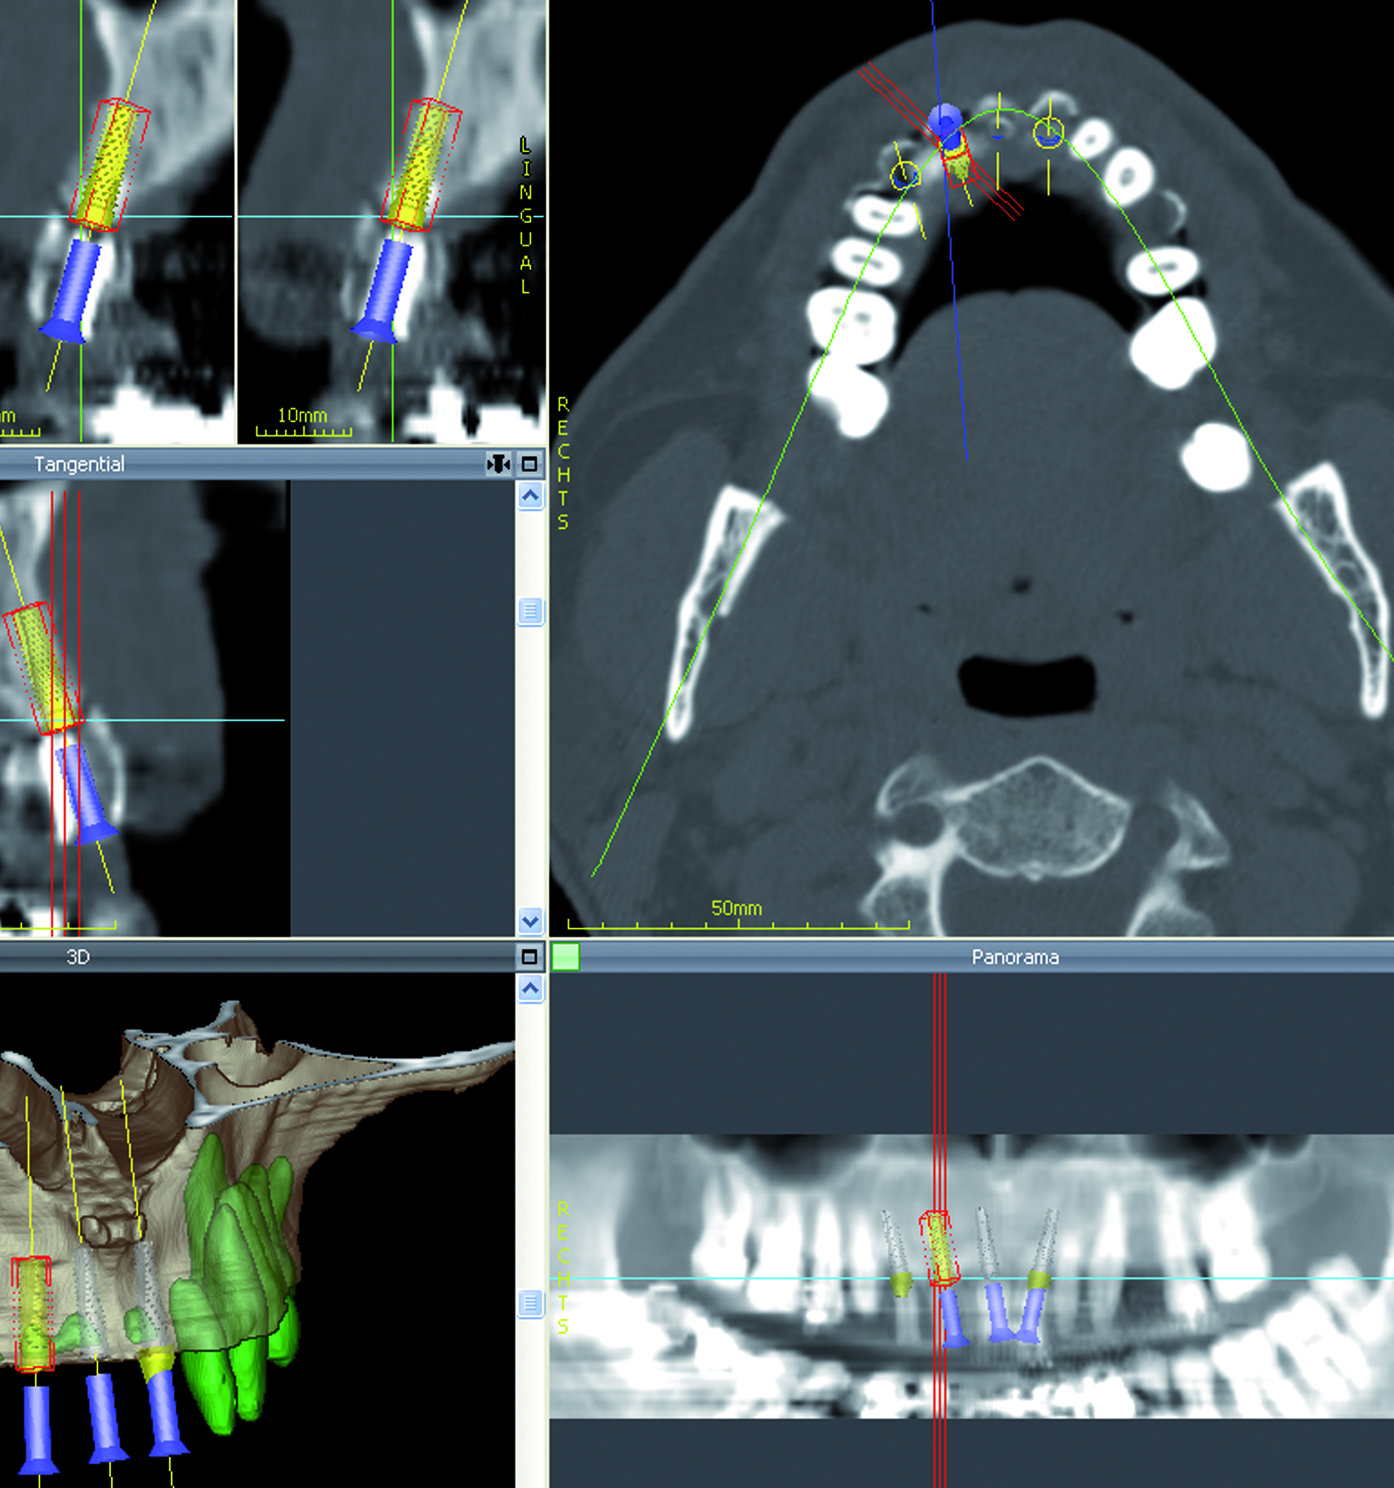

PLANUNGSSOFTWARE coDiagnostiX

Wir arbeiten mit der Planungssoftware coDiagnostiX der Firma Dental Wings. coDiagnostiX steht für Vision, Innovation und Perfektion auf dem Gebiet der dreidimensionalen Implantatplanung.